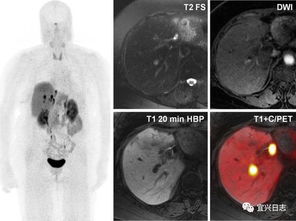

惡性腫瘤細胞由于代謝旺盛而對葡萄糖的需求增加,因此18FDG后,大多數(shù)腫瘤病灶會表現(xiàn)為對18FDG的高攝取,因此可應用18FDG

PET-CT顯像可早期發(fā)現(xiàn)全身腫瘤原發(fā)及轉移病灶,準確判斷其良、惡性,從而正確指導臨床治療決策。但是18F-FDG有著放射性核半衰期,這就總讓受檢者們擔心,做完PET